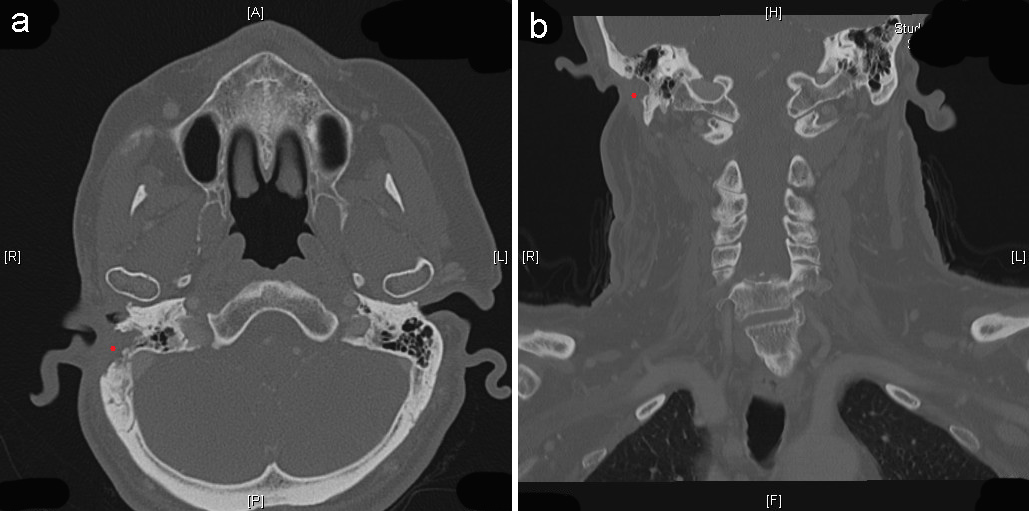

Nevertheless, three years later, the patient returned to the clinic with a recurrent retroauricular swelling, which infiltrated the sternocleidomastoideous muscle and caudally the external meatus acusticus. Preoperative audiometry revealed a basocochlear labyrinthine hearing loss (presbyacusis). Following magnetic resonance imaging (MRI) (Figure 1 [Fig. 1]), histopathological confirmation, and multidisciplinary discussion of treatment options, a radical tumor resection was performed. The procedures consisted of a subtotal concha ablation, radical parotidectomia, as well as removal of caudal part of the external meatus acusticus and cranial part of the sternocleidomastoideus muscle as en-bloc resection. Additionally, for the purpose of evaluating safety margins, a lateral mastoidectomia was deemed necessary (Dr. M. Herzog is acknowledged; follow-up computer tomography [CT] in Figure 2 [Fig. 2]). Owing to peripheral facial nerve palsy, a lateral canthoplasty was simultaneously performed [10]. On account of an 8x9 cm resection defect, an ipsilateral pedicled myocutaneous latissimus-dorsi flap was raised. The postoperative period was uneventful, and following primary wound healing, adjuvant radiotherapy ad 64Gy was applied.

Figure 2: a: Follow-up imaging – axial computerized tomography (CT) section. Red asterisk indicating the partially resected right mastoid process. b: Follow-up imaging – coronal CT section. Red asterisk indicating the partially resected right mastoid process.